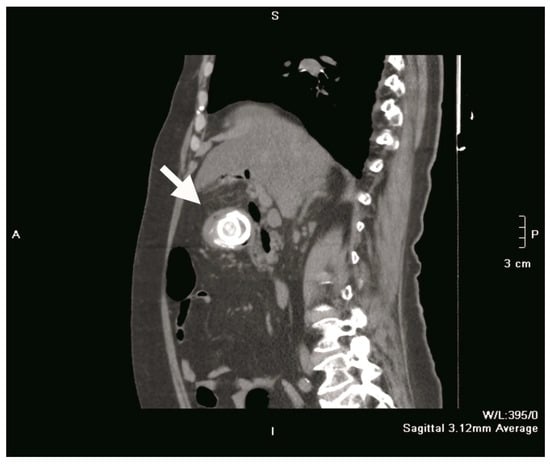

Figure 2.

Sagittal section CT scan showing a gallstone (white arrow) impacted in the duodenal bulb.